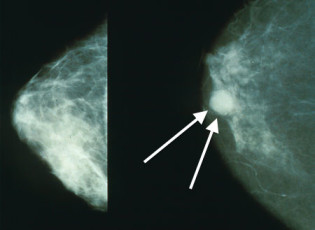

- Peter Byrne, investigative reporter and science writer based in Petaluma, author of a 10-part investigative series called Busted! Breast Cancer, Money, and the Media that is running in the Point Reyes Light